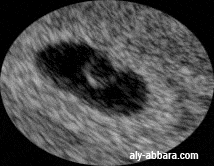

| L'activité cardiaque d'un embryon mesurant

(1,5) mm de longueur crânio-caudale et âgé de de 20 et 23 jours selon les Horizons (stades) de G.L. Streeter (1942- 1948)( ou 5 SA à 5 SA et 2 jours) Il s'agit presque, le premier jour de l'apparition de l'activité cardiaque chez l'embryon Embryologiquement les battements cardiaques apparaissent au environ du 21e jour de gestation (5 SA). |

| L'image

montre :

le sac gestationnel entouré par le tissu trophoblastique

; on peut distinguer les vaisseaux sanguins parcourant le plan de

l'insertion du tissu trophoblastique sur l'endomètre ;

l'embryon avec la vésicule vitelline ; ils sont situés au niveau

du pôle supérieur de la cavité cœlomique ;

l'activité cardiaque embryonnaire.